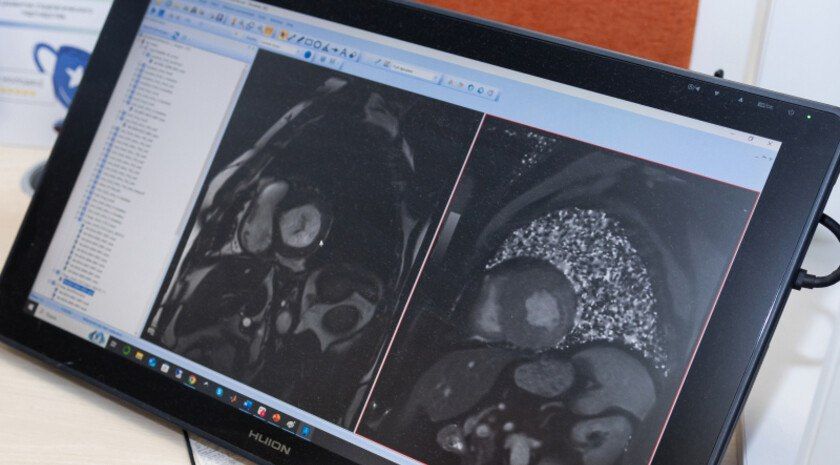

Ученые Университета ИТМО разработали комплекс с элементами ИИ для обработки МРТ-снимков, который позволяет всего за несколько минут проверять сердце на наличие фиброзных тканей. Об этом сообщила пресс-служба вуза.

«Ученые ИТМО совместно с коллегами из НМИЦ им. Алмазова придумали, как быстро определять фиброз сердца с помощью глубокого обучения. Для этого они разработали алгоритм, который делит изображение сердца на 17 сегментов, а затем определяет расположение и количество фиброзной ткани. Разработка освободит врачей от сложной работы по обработке МРТ-снимков и ускорит подбор наиболее эффективной стратегии лечения инфаркта и других заболеваний сердца», — говорится в сообщении.